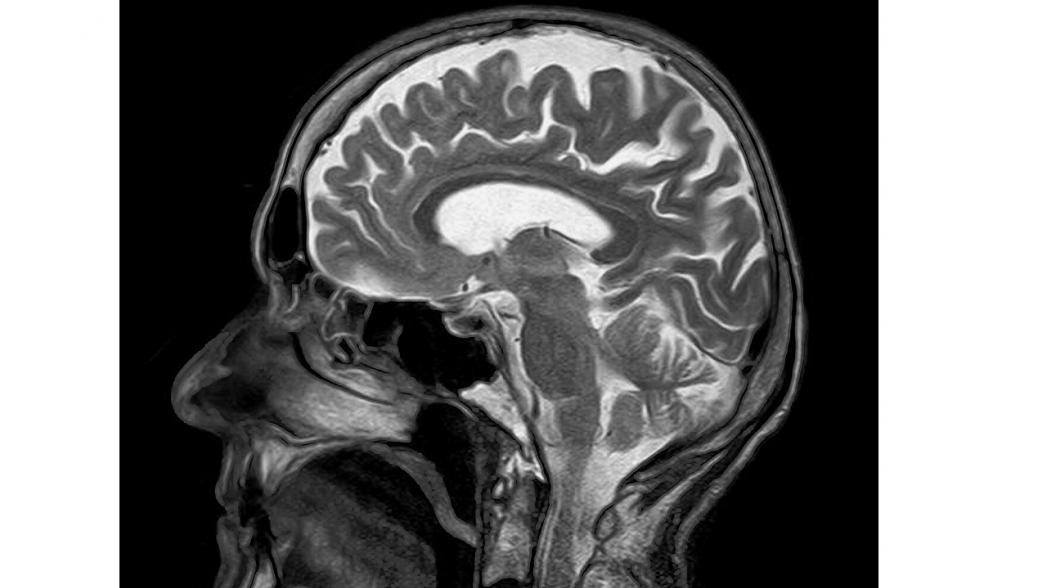

Еще находящаяся в стадии разработки система DeepSpin будет представлять собой МРТ-систему нового типа, которая будет существенно меньше по весу и размеру существующих систем, а ее цена составит всего лишь долю стоимости современных МРТ-аппаратов. Для того, чтобы это было осуществимо, специалисты компании разработали новую технологию антенны, а также программное обеспечение управления работой системы на основе алгоритмов искусственного интеллекта.

Вместо того, чтобы комбинировать дорогостоящее оборудование со стандартным программным обеспечением, как это делается на обычных МРТ-сканерах, новая система позволяет получать клиническую информацию такого же качества, применяя очень сложные алгоритмы на упрощенном аппаратном обеспечении, тем самым снижая стоимость системы на порядки величины.

Разработчики утверждают, что их разработка обладает производительностью и качеством, такими же как стандартные МРТ–аппараты, не требует специального обслуживания, поскольку не использует гелий и может применяться в любом месте, включая больничные палаты.